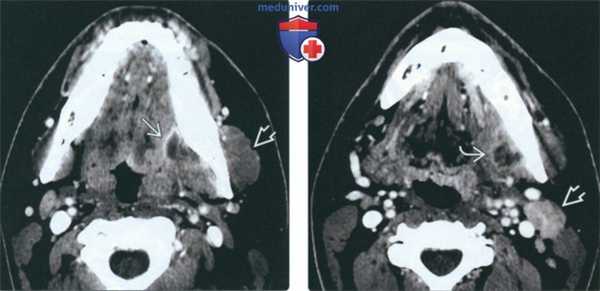

(Слева) На аксиальной КТ с КУ определяется большой многокамерный абсцесс внутреннего ЖП с вовлечением крыловидных мышц. Обратите внимание на утолщение и отек жевательной мышцы в наружном жевательном пространстве. У этого пациента 21 года девять месяцев назад был удален моляр слева, после чего появилась оталгия в сочетании с тризмом, неверно расцененные как проявления синдрома ВНЧС.

(Справа) На аксиальной КТ с КУ у этого же пациента определяется дальнейшее распространение абсцесса внутреннего ЖП в и отек жевательной мышцы.